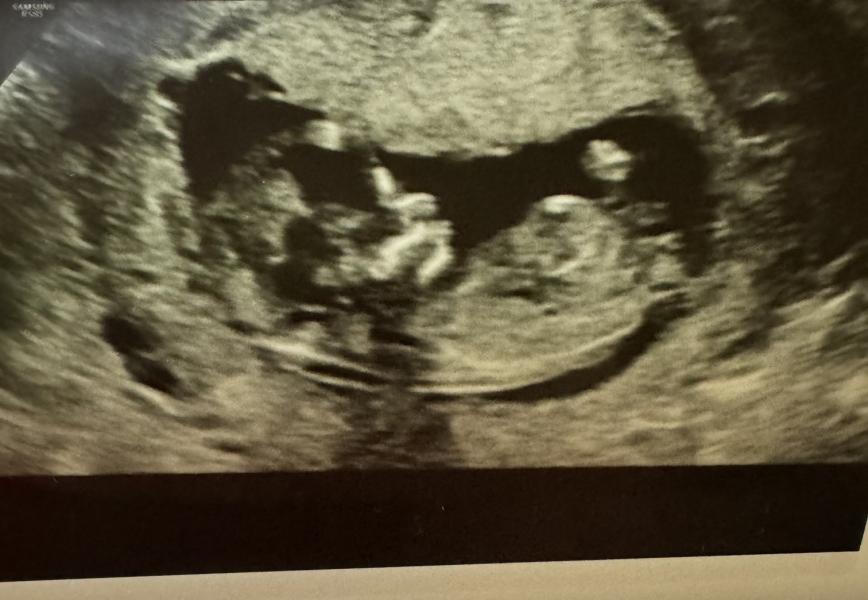

Первый скрининг❤️

Девочки, мы прошли скрининг) по узи все замечательно, носик визуализируется, все объемы соответствуют сроку.

Ну а еще, нам сказали, что у нас будет сын❤️

Ну что за сладкий человечек на фотках!😍❤️

Очень рада, что еще один маленький, но очень важный этапик пройден!🙏🏻

Это так мило!!!☺️ 🥹🥹